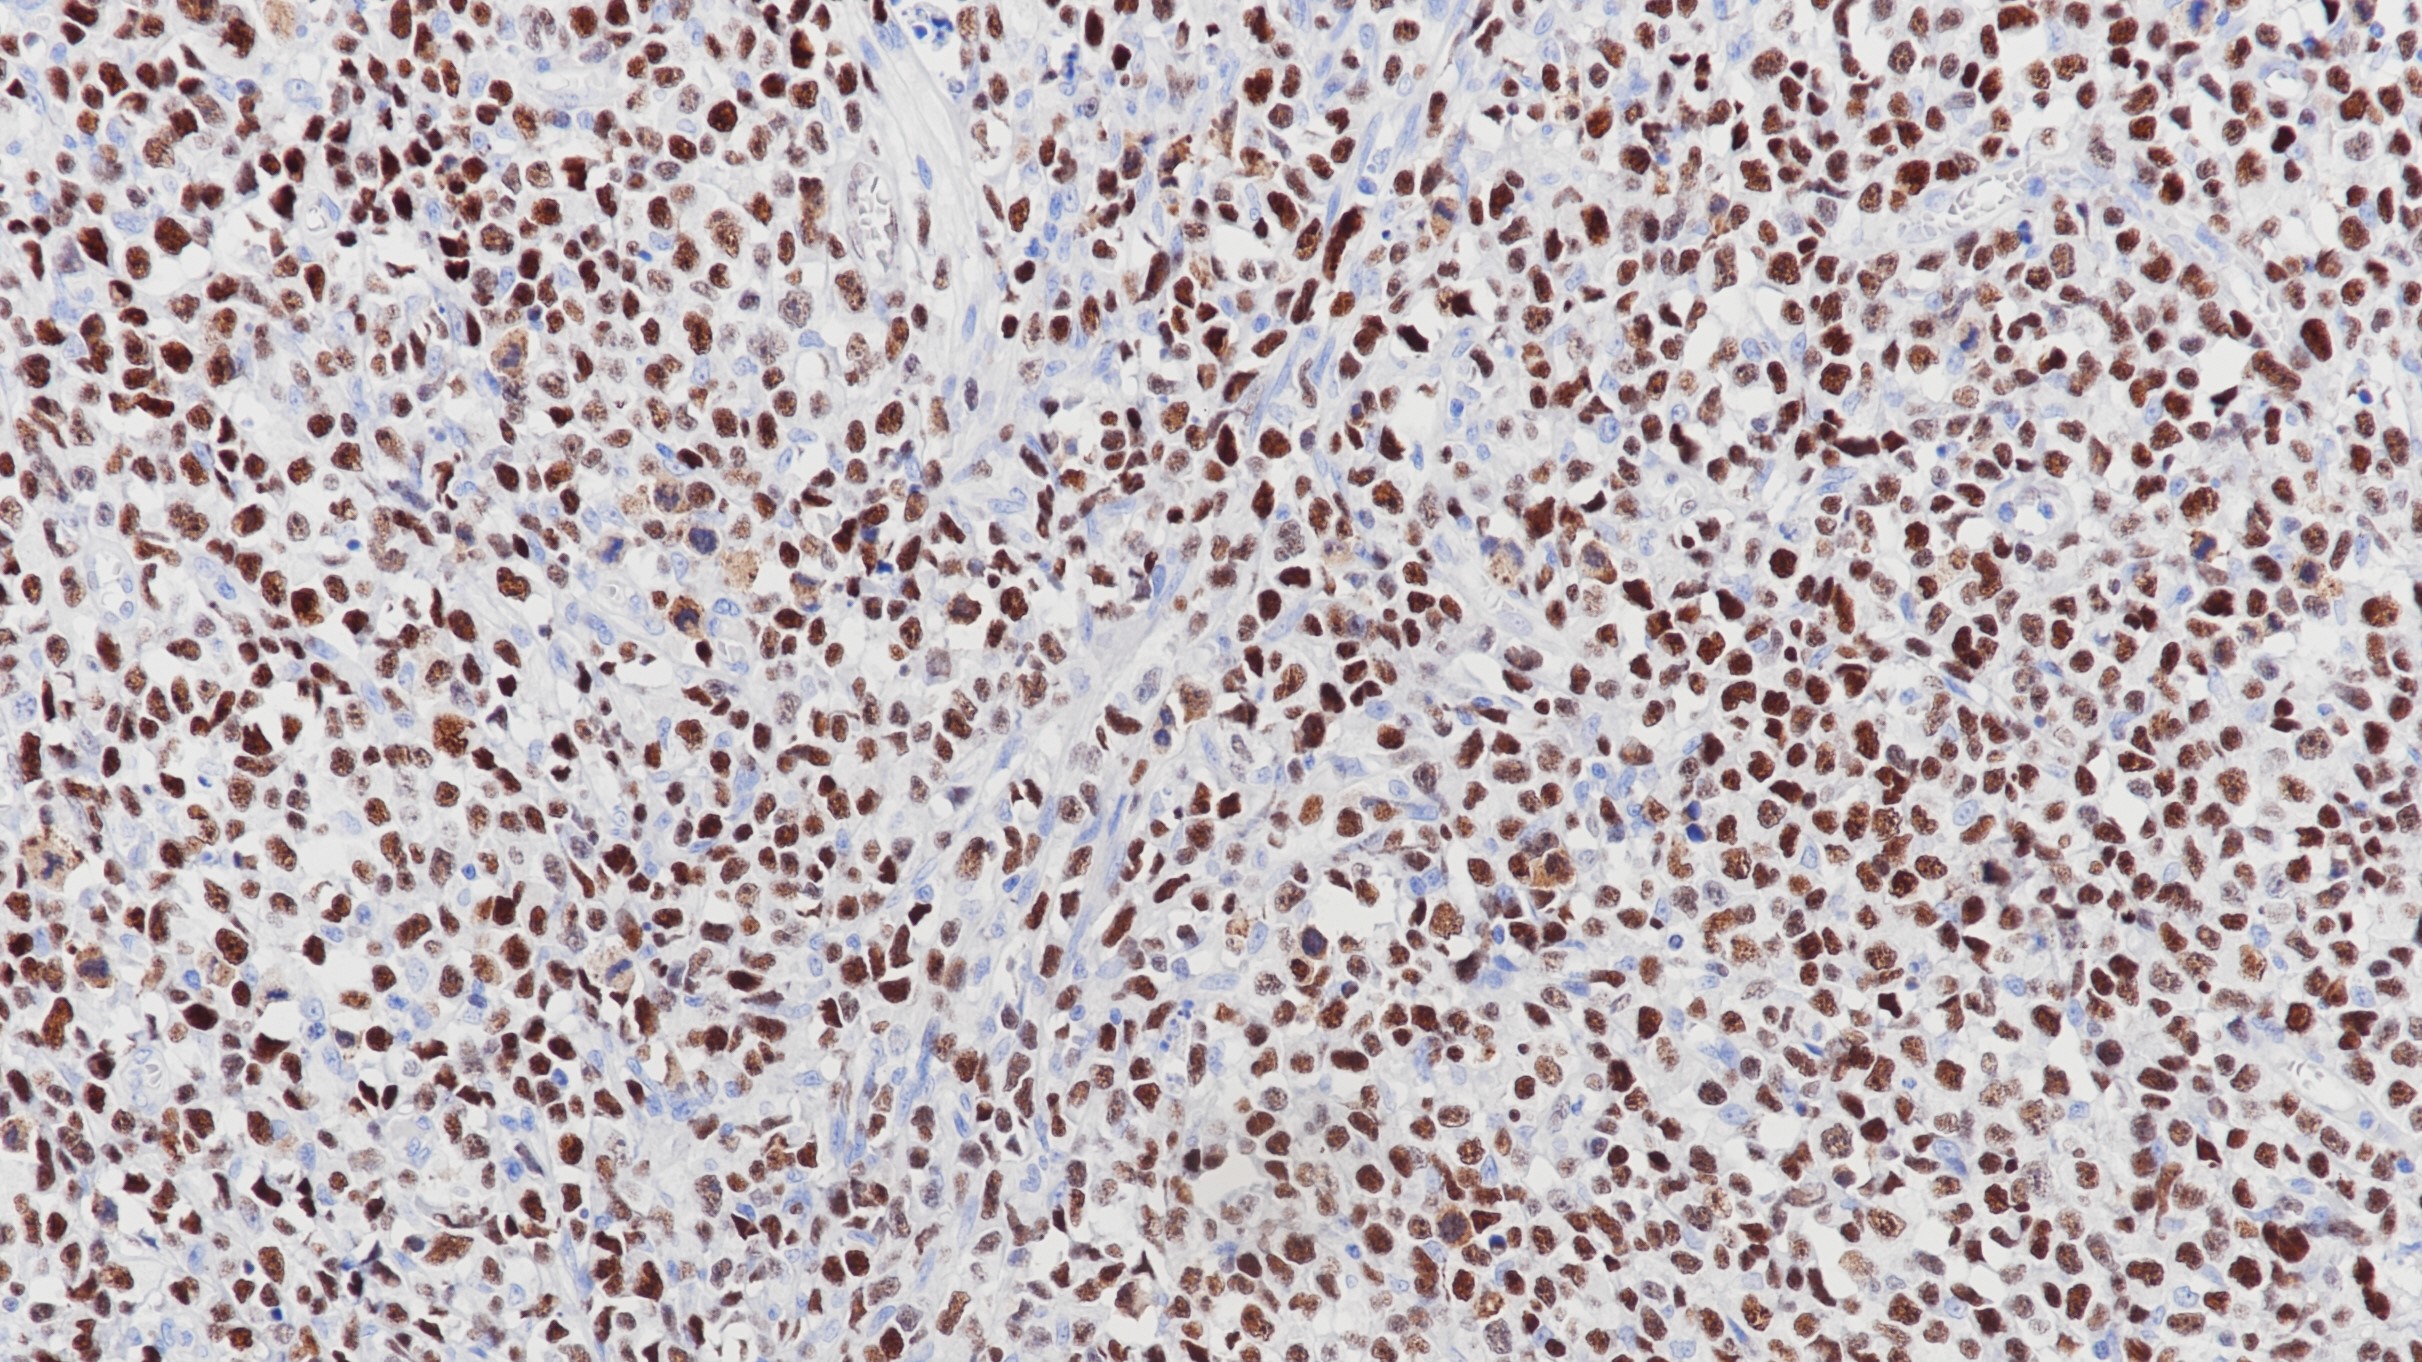

IgM是B淋巴细胞表面主要的免疫球蛋白之一,该抗体可以与免疫球蛋白IgM的μ链反应,对一些淋巴瘤的鉴别诊断具有一定的辅助意义,也可用于对肾小球肾炎进行功能性分类。

阳性对照

扁桃体